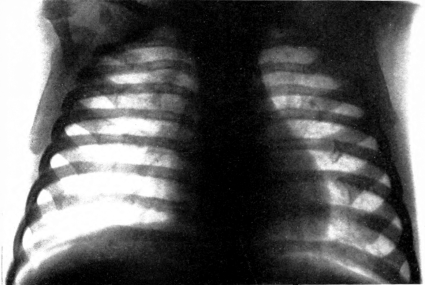

| 19. | Scorbutic beading of ribs. Roentgenogram | 198 |

| 20. | “White line.” Roentgenogram | 199 |